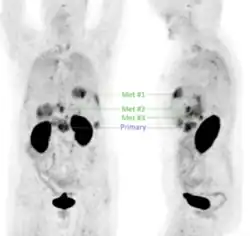

Neuere Forschungen setzen sich intensiv mit der Anwendung der Positronen-Emissions-Tomographie (PET) für die Bildgebung des (duktalen) Pankreaskarzinoms (PDAC) auseinander, wobei das Interesse insbesondere auf die Detektion von Metastasen fokussiert ist. Für PET ist die intravenöse Gabe eines Radiotracers erforderlich, also eines Radiopharmakons, welches mit einem Positronen emittierenden Radionuklid markiert ist. Der für die PET am häufigsten eingesetzte Tracer, 18F-Fluordesoxyglucose (FDG) ist jedoch für die Diagnostik des PDAC nur bedingt geeignet, da dessen vergleichsweise langsames Wachstum und die desmoplastische Gewebsstruktur oft dazu führt, dass FDG zu gering angereichert wird, um eine verlässliche PET-Diagnostik zu gewährleisten.[43] Die Tumorzellen von PDAC weisen jedoch in den meisten Fällen (>88 %) eine Überexpression des Oberflächenproteins αvβ6-Integrin auf, weshalb Radiopharmaka, die spezifisch an dieses Protein binden, für die PET-Bildgebung von PDAC genutzt werden können.[44] Im Zuge der experimentellen klinischen Anwendung verschiedener αvβ6-Integrin-gerichteter Radiotracer zeigte sich, dass 68Ga-Trivehexin[45] gut für die PET-Bildgebung des metastatischen PDAC geeignet sein könnte (siehe Beispielbild), insbesondere aufgrund der vergleichsweise geringen unspezifischen Anreicherung im gastrointestinalen Bereich.[46] Infolgedessen wurde 68Ga-Trivehexin experimentell für die PET-Bildgebung in einigen PDAC-Fällen[47][48][49] sowie einer größeren Kohorte (44 Patienten)[50] mit PDAC oder Verdacht auf PDAC erfolgreich diagnostisch angewendet.